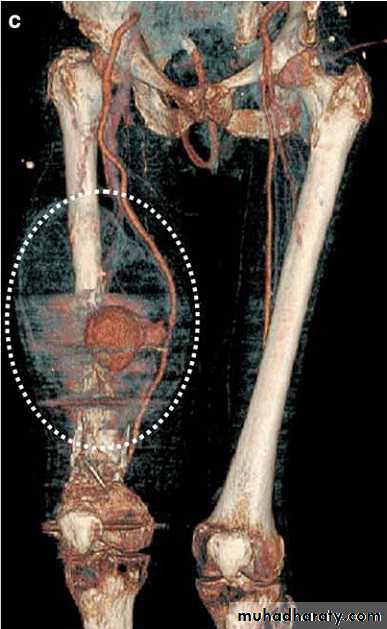

2. Duplex scan3. CT ANGIOGRAPHY - Helps to locate, to assess the extent of injury, to identify associated injuries and to plan the treatment.

4. On table angiography - in cases needing urgent exploration and having multilevel injuries. i.e trap gun injury